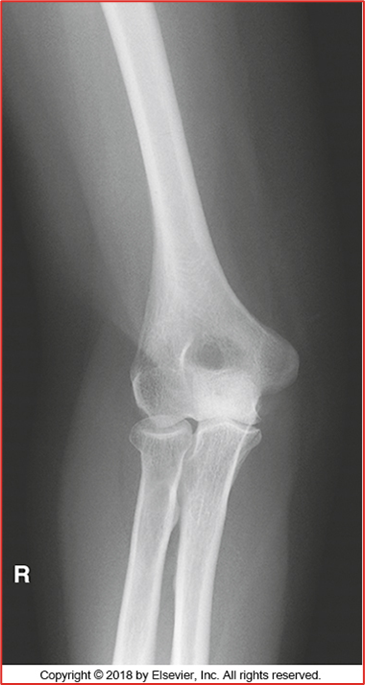

these 2 elbow images are in what position (2 for 1!!)

in this AP Partial Flexion is the humerus or forearm parallel

-All anatomy present (humerus, radius, and ulna)

-Only should be partial superimposition of the radius and ulna (this image they are fully separated)

-They are laterally rotated (fix by medially rotating them and feeling the epicondyles)

-Epicondyles not perfectly in profile (due to rotation)

-Olecranon in olecranon fossa

-Open Joint Space = pretty good

-No crowning of radial head (good)

• REPEAT

Critique this AP Elbow Image